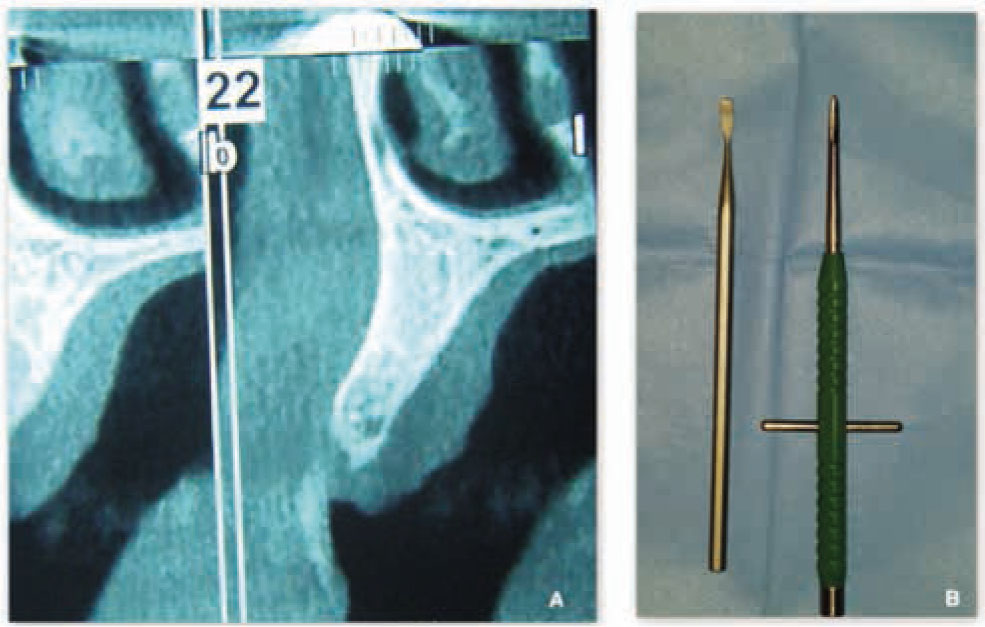

Orthopantomography and CT DentaScan/CT Cone beam were performed for every patient before treatment. In test group-1 autologous PRF was used to fill the split crest gap as regenerative material.

An orthopantomography and CT DentaScan/CT Cone beam were performed for every patient before surgery to have a preliminary radiological investigation and to get a general overview of the jawbones and relevant anatomic landmarks in a bi-dimensional plane (Figure 5). Also intraoral and face photographs were taken pre-operatively for aesthetic and functional evaluation of the patients status. For all the patients a beta-lactam antibiotic (Amoxicillin) was given orally, 2gr. one-hour before surgery. Post-operative therapy required good oral hygiene, rinsing with mouthwash containing 0.2% chlorhexidine solution twice a day and an evening application of the same product in gel form, as well as the administration of a non-steroidal anti-inflammatory drug (Ketoprofen 80mg) for three consecutive days.